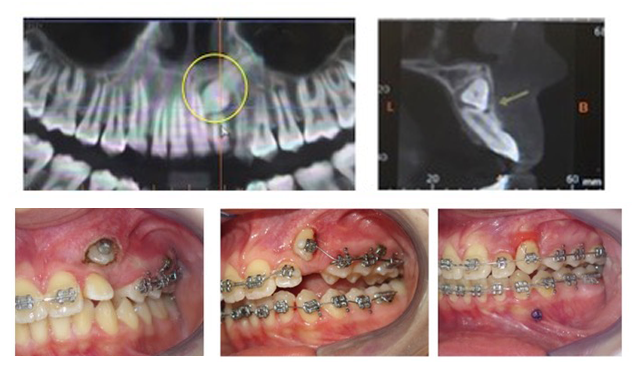

Toplumumuzda sıklıkla 20 yaş dişlerinden başka köpek dişleri ve daha az sık olarak da küçük azı dişleri üst ya da alt çenede gömük kalabilmektedir. Bu durum genç yaşta bir ortodontist takibinde olan kişilerde erken tedavilerle engellenebilecek bir durum olduğu gibi çoğu zaman gençlik döneminde ya da daha ileri yaşlarda başka bir şikayet için yapılan radyolojik muayenelerde tesadüfen tespit edilir. Bu durumlarda bir ortodonti uzmanı tarafından yapılan muayeneyle gömük olan dişin doğal diş dizilimi içine ortodontik tedavi ile çekilerek yerleştirilmesinin mümkün olup olmadığına karar verilir ve mümkünse, hasta da bu tedaviyi onaylamışsa braketler ve teller takıldıktan sonra daha ileri bir seansta gömük olan dişin üstü lokal anestezi altında minik bir cerrahi işlemle açılır ve dişe bir metal düğmecik yapıştırılır, bu metal düğmeye bağlanan bir tel de ağızdaki dişler üzerinde takılı olan braketler ve tel sistemine bağlanarak diş yavaş yavaş doğal yerine doğru çekilerek pozisyonlandırılabilir.

Bu tedaviler genelde oldukça uzun süreli (minimum 2 yıl) tedavilerdir ve dişin sürdürülmesi her zaman mümkün olmayabilir. Bazı durumlarda gömük dişin pozisyonu, gömüklük derecesi, engel komşu dişlerin kökleri vb. sebeplerden ortodontik olarak yerine getirilemeyeceği karar verilebilir, bu durumda gömük diş çekilip boşluğu ortodontik olarak kapatılabilir ya da implant ile bu boşluk restore edilebilir.Hasta için en doğru olan yol tercih edilir.Bazen de bu dişler çene içinde bırakılabilir, bu durumda yıllık düzenli radyolojik muayenelerle diş takibe alınır. Bu kararı da tercihen ortodonti uzmanı almalıdır.